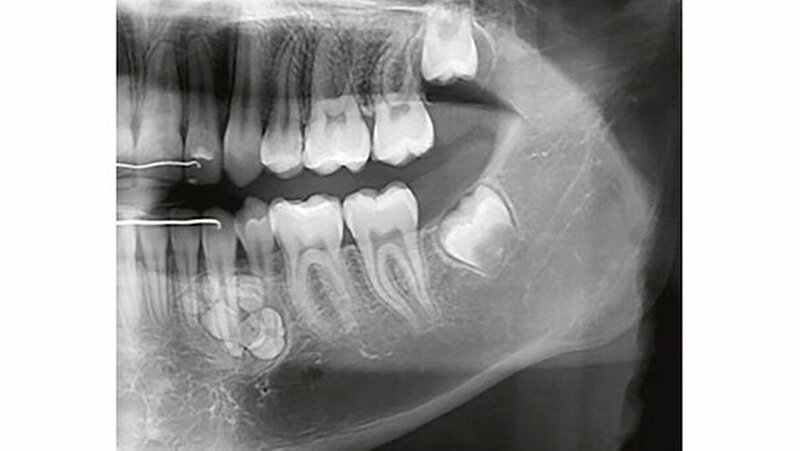

Auf dem mitgelieferten vier Jahre zuvor erstellten Orthopantomogramm (OPT) waren noch keine Hinweise auf das Vorhandensein einer Veränderung regio 32-34 sichtbar (Abbildung 2). Ein Jahr später konnte anhand des OPT bereits eine radioopake Struktur regio 33, 34 festgestellt werden (Abbildung 3). Auf dem aktuellen OPT und digitalen Volumentomogramm (DVT) zeigten sich regio 32-34 lingual multiple, rundliche, unterschiedlich große Radioopazitäten, umgeben von einer radioluzenten Zone.

Die Ränder der radioluzenten Zone waren sehr gut zum umgebenden Alveolarknochen abgrenzbar (Abbildung 4, 5). Eine dreidimensionale Diagnostik (DVT) macht aus dreierlei Gründen Sinn: 1. Erleichterung der Patientenaufklärung, 2. optimale Lagebestimmung des Tumors in Bezug zu benachbarten anatomischen Strukturen wie Nachbarzähne und Nerven, 3. präoperative Bestimmung der Anzahl zahnähnlicher Strukturen (zusammengesetztes Odontom), um kontrollieren zu können, ob während des operativen Eingriffs alle hartgewebigen Tumoranteile entfernt worden sind.